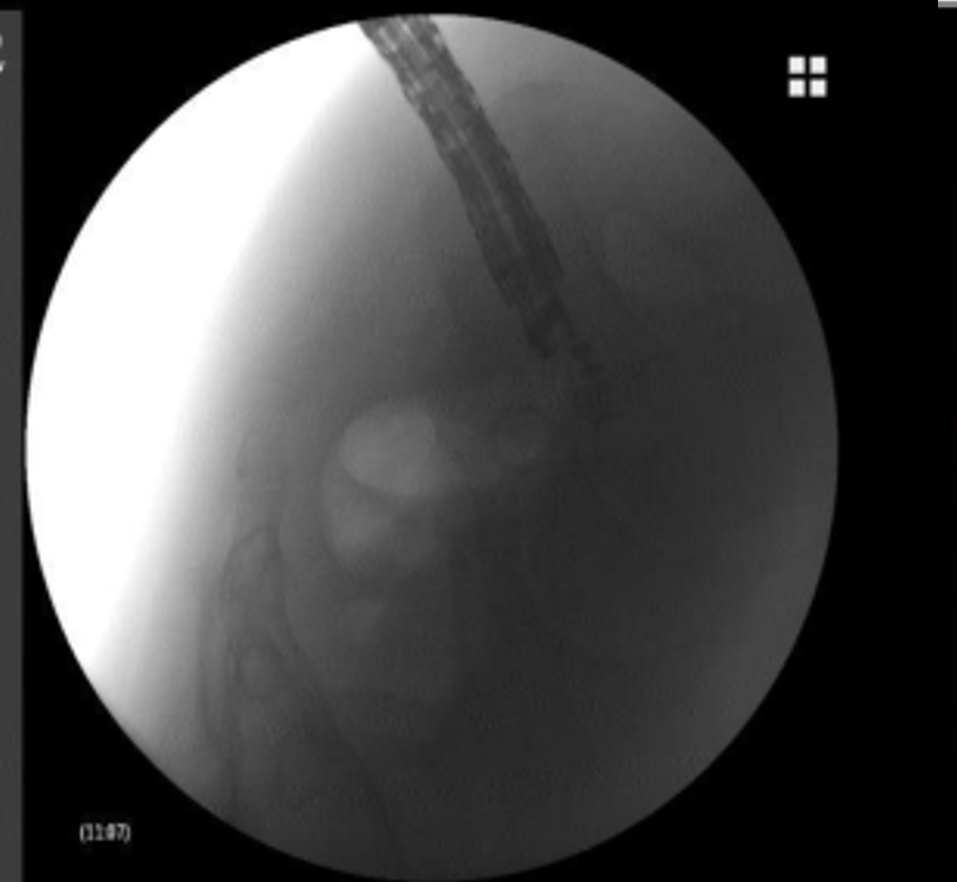

支架置入过程

经过充分的术前准备,消化内科刘华副主任医师在毛涛主任的指导下,和麻醉科、内镜室医护团队的密切配合下,凭借精湛的内镜技术,仅用时20分钟,便通过实时超声精准锁定病灶位置,巧妙避开血管、神经等重要解剖结构,合理规划穿刺路径并成功置入支架。手术全程经人体自然腔道操作,无体表切口,且未对直肠功能造成损伤。